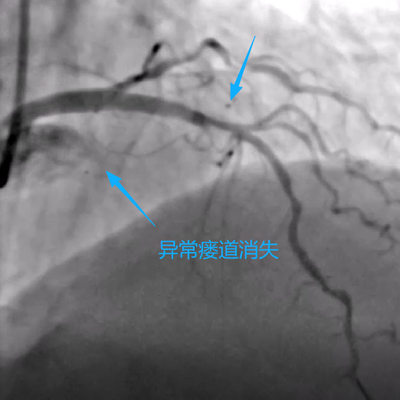

手术当日,在数字减影血管造影(DSA)设备的精确引导下,手术团队通过患者手腕部仅有米粒大小的穿刺点,将一根细如发丝的微导管,犹如“穿针引线”般精准送达深藏在心脏的异常瘘管内。随后,通过导管将栓塞物质置于瘘管的关键部位,成功实现了对异常通道的“精准封堵”。术后即刻造影显示,异常血流分流完全消失,被“盗走”的血液重新回到了正常的冠脉轨道,手术取得圆满成功。(如下图)

“整个手术过程患者处于清醒状态,创伤小、痛苦少、恢复快。” 心血管内科朱兴彪主任表示,“术后第二天,患者即可下床活动,之前胸闷气促的症状得到了立竿见影的缓解,患者和家属都非常满意。”